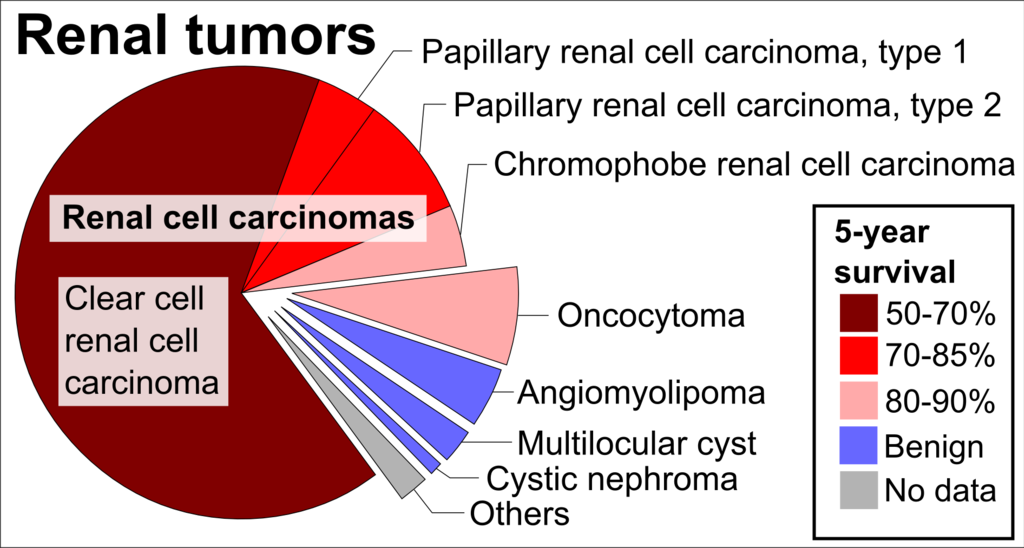

Renal Cell Carcinoma (RCC)

Renal cell carcinoma (RCC) is a malignant cancer cells are located in the lining of kidney tubules, which are incredibly tiny tubes. This condition is known as renal cell carcinoma.

When examined under a microscope, the most common variant of renal cell carcinoma shows clear cytoplasm or a clear cell type.

Renal cell carcinomas (RCCs) may be hereditary or sporadic.